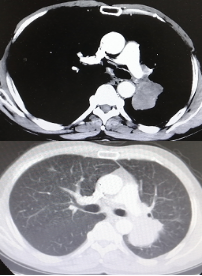

治疗9周期后,病灶增大30%,疗效评估为PD。

靶病灶:左肺病灶增大;

非靶病灶:右肺门较前相仿。

CT检查——治疗9周期后

治疗8周期后,左肺病灶较前增加,疗效评估为PD。

CT检查——治疗8周期后

综合来看此次治疗过程中,靶病灶变化情况先缩小再增大。